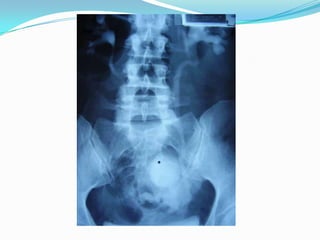

DIAGNOSTICOURETROCISTOGRAFIA RETRÓGRADA efectuada con inyección de contraste de 400 cc., es el GOLD STANDART.Alternativa: cistografía por TC Si hay uretrorragia, efectuar uretrografia retrógrada y urograma excretor para descartar otra lesión del árbol urinarioEn las roturas extraperitoneales con fracturas, en placa post miccional se observa la extravasación del medio de contraste al escroto.

DIAGNOSTICOURETROCISTOGRAFIA RETRÓGRADA efectuadacon inyección de contraste de 400 cc., es el GOLD STANDART.Alternativa: cistografía por TC Si hay uretrorragia, efectuar uretrografia retrógrada y urograma excretor para descartar otra lesión del árbol urinarioEn las roturas extraperitoneales con fracturas, en placa post miccional se observa la extravasación del medio de contraste al escroto.